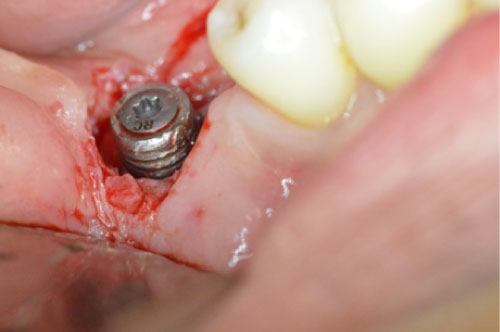

A 41-years-old patient presented with a restored dental implant in the mandibular posterior molar area, the implant fixture was placed approximately eight years ago and restored few months afterwards. The intra-oral exam revealed 5-6 mm pockets around the implant with slight inflammation of the surrounding soft tissue including bleeding upon probing and exudate. No mobility was detected and the patient was asymptomatic. The radiographic exam (Figure 1) revealed considerable bone loss with no other findings. The implant crown was removed and a cover screw placed. The Surgical treatment included a circumferential incision around the implant (Figure 2) followed by excavating the granulation tissue into the bony defect, scaling the implant surface using ultrasonic scalers and then using Prefgel to decontaminate the implant surface (Figure 3). A bone mix of mineralized cortico-cancellous allograft with Amnion-Chorion strips used to fill the bone defect (Figure 4 and Figure 5) and followed by mono filament non-resorbable suture (Figure 6). The patient placed on systemic antibiotics for one week and was prescribed chlorhexidine mouth wash in addition to mild analgesics. Two weeks post-operatively the patient presented with uneventful healing of the soft tissue and complete healing of the surgical wound over the bone graft mass (Figure 7). Three months following the procedure a periapical film showed considerable fill of the bone defect with integration to the implant surface (Figure 8).

Figure 2: Circumferential incision around the implant with removal of the granulation tissue. View Figure 2